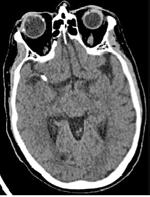

Paciente de 61 años con antecedentes de fibrilación auricular (FA) de reciente diagnóstico no anticoagulada por CHA2DS2VA 0. Consulta en Urgencias el día 16/02/2022 por afasia. A su llegada el paciente se encuentra asintomático, sin embargo, mientras permanece en Urgencias vuelve a presentar un nuevo episodio de afasia. A la exploración física, además de la afasia, presenta anestesia de toda la extremidad superior derecha. Se activa código ictus y se hace un angioTAC craneal, que muestra una oclusión de la rama M1 de la arteria cerebral media izquierda de perfil cardioembólico. Se decide iniciar tratamiento fibrinolítico y tratamiento endovascular, recanalizando la rama M2 de la arteria cerebral media mediante el implante de un stent retriever al cuarto intento. Tras ello, el paciente pasa a la Unidad de Ictus con mejoría sintomática.

El día 18/2/2022 el paciente refiere dolor torácico. Se realiza un electrocardiograma, que muestra elevación del segmento ST en las derivaciones anteriores en relación con un infarto agudo de miocardio (IAM) anterior. Se activa código infarto y se realiza una coronariografía emergente, que muestra una oclusión de perfil embólico en la arteria descendente anterior media (Figura 1, flecha amarilla). Se trata con trombectomía aspirativa con buen resultado angiográfico final con flujo TIMI 3. Se inicia tratamiento con perfusión de heparina sódica. El día 19/2 el paciente comienza con cefalea muy intensa y afasia, por lo que se activa nuevamente código ictus y se realiza un angioTAC craneal que muestra una hemorragia subaracnoidea (HSA) de predominio izquierdo secundaria a sangrado por un aneurisma disecante de la rama M2 de la arteria cerebral media izquierda (Figura 2, flecha amarilla). Se decide completar estudio con una angiografía que confirma los hallazgos del TAC. Por el alto riesgo de resangrado y la necesidad de anticoagulación oral permanente, se decide embolización del aneurisma con coils, que resulta exitoso (Figura 3, flecha amarilla). Se reinicia durante el ingreso perfusión de heparina sódica y unos días antes del alta se comienza con anticoagulación oral con apixaban 5 mg/12 horas. La evolución clínica es favorable, siendo la exploración física al alta normal. Tras tres años de seguimiento bajo tratamiento con apixaban 5 mg/12 horas no han sido reportados nuevos episodios de sangrado ni de trombosis.